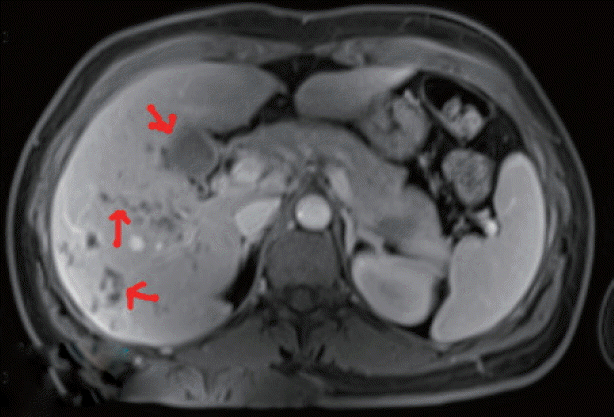

In June 2016, detailed clinical, laboratory, and radiographic tests were performed in Fuzhou General Hospital of Nanjing Military Region, Nanjing, China. Laboratory tests revealed high eosinophilia, mild normocytic normochromic anemia, and high serum activity of alkaline phosphatase (ALP), with normal alanine aminotransferase (ALT) and aspartate amino transferase (AST) levels. MRI showed hypodense changes (total diameter up to 6 cm) in both liver lobes below the diaphragm, predominantly localized posteriorly and centrally (Fig. 1).

Migration of juvenile Fasciola through the liver in the invasive stage could cause hepatic lesions. Pathological sections show micro-abscesses and tunnel-like areas of parenchymal necrosis [31]. Imaging should be applied as auxiliary diagnosis, which may show abscesses and tunnels caused by the migrating young flukes or those in the biliary passage (chronic infection) [32]. The abdominal MRI finding in the current patient showing hypodense clustered lesions on the periphery of both hepatic lobes was compatible with the hepatic phase of fascioliasis. However, images seen on ultrasound and CT may sometimes be confused with malignancy or stones. The most useful diagnostic test for detecting the bile ducts is cholangiography by endoscopic retrograde cholangiopancreatography (ERCP). ERCP is quite important in evaluating symptomatic patients, especially in those with cholestatic syndrome, colicky pain, and abnormal liver function, or those in whom the parasitic disease has caused systemic involvement [33].